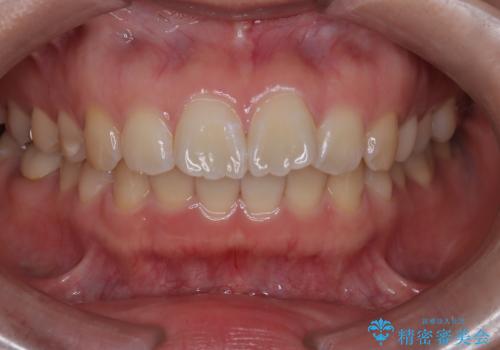

繰り返すプラスチックの欠けを解消。広範囲の修復に適したセラミッククラウン

担当医 河口智英